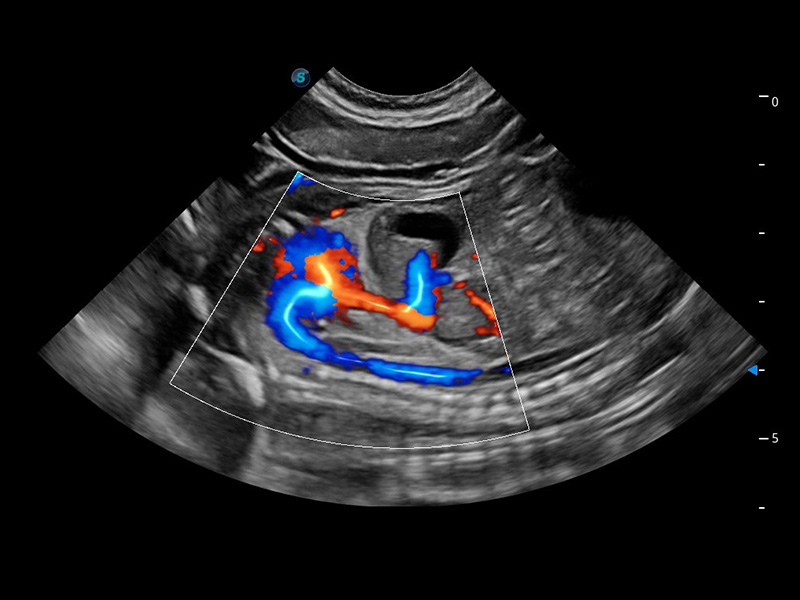

ProPet 60 作为一款高端台式动物超声设备,为动物医生的日常诊断提供了一系列贴合动物临床需求、解决临床实际问题的高级成像功能。凭借全系列高清探头,满足医生对腹部、心脏、生殖、浅表、肌骨等成像的所有需求,切实帮助您提升检查效率,提高诊断信心。

动物是人类最亲密的朋友和最值得信赖的伙伴。哈哈体育官网也一直致力于探索动物专用的超声影像解决方案。 全新推出的ProPet系列,是哈哈体育官网在动物超声影像智能化、专业化、精准化的一次跨越式革新。动物不能用言语来表述自己的不适,通过超声影像,ProPet系列搭建了动物医生与不同物种沟通的“桥梁”,为动物医生注入了“治愈之力”。